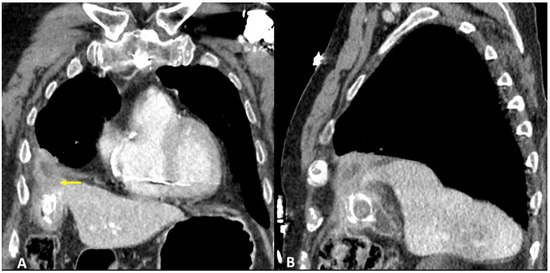

3.3. Case #3: Hepato-Thoracic Fistula